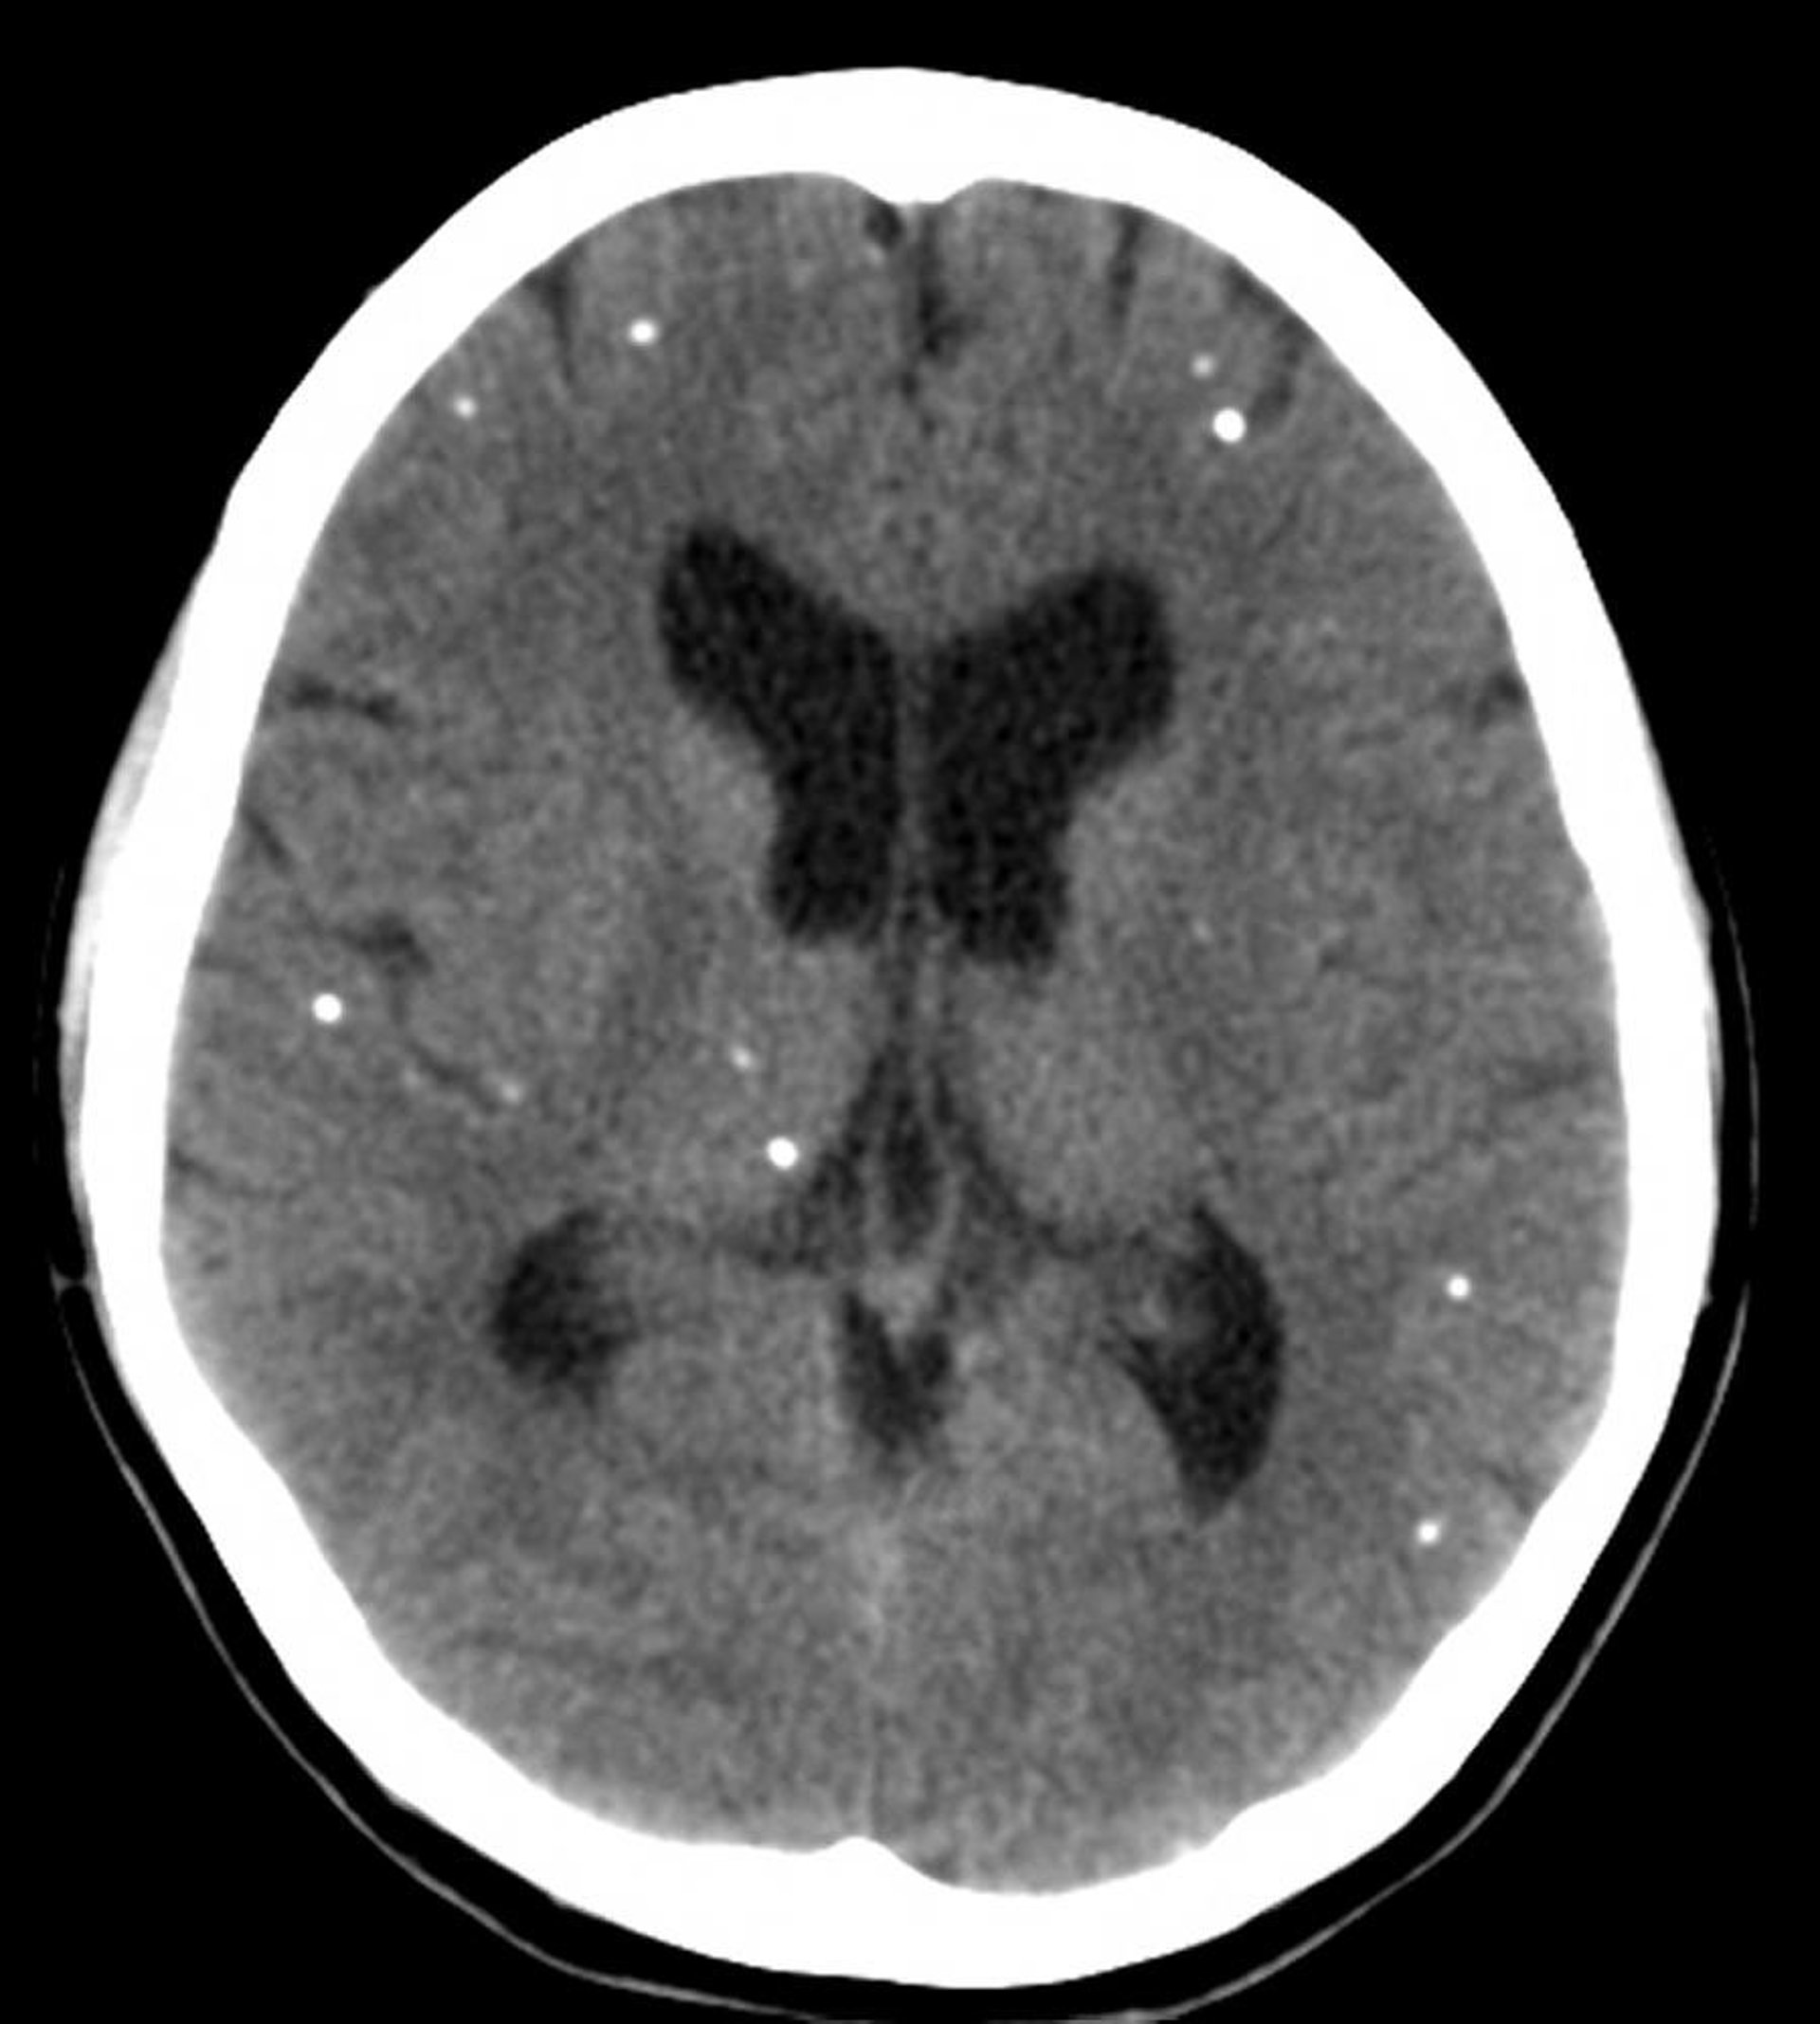

Neurocisticercosis

Esta TC muestra áreas multifocales de calcificación que representan quistes calcificados en un paciente con neurocisticercosis.

Courtesy of John E. Greenlee, MD.